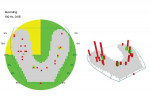

Utilizing the OccluSense for guidance, the clinician equilibrated the patient's occlusion and was able to create a balanced and protected occlusion (Figure 12). After the patient was in the temporary prosthesis for several weeks, he confirmed that the occlusion functioned well. At that point, a new final full-arch prosthesis was delivered to the patient. This new prosthesis is currently functioning very well and the patient's occlusion has been corrected. The OccluSense provides invaluable information, especially when it relates to fixed or removable full-arch prostheses, turning long and frustrating occlusal equilibrations into predictable appointments.